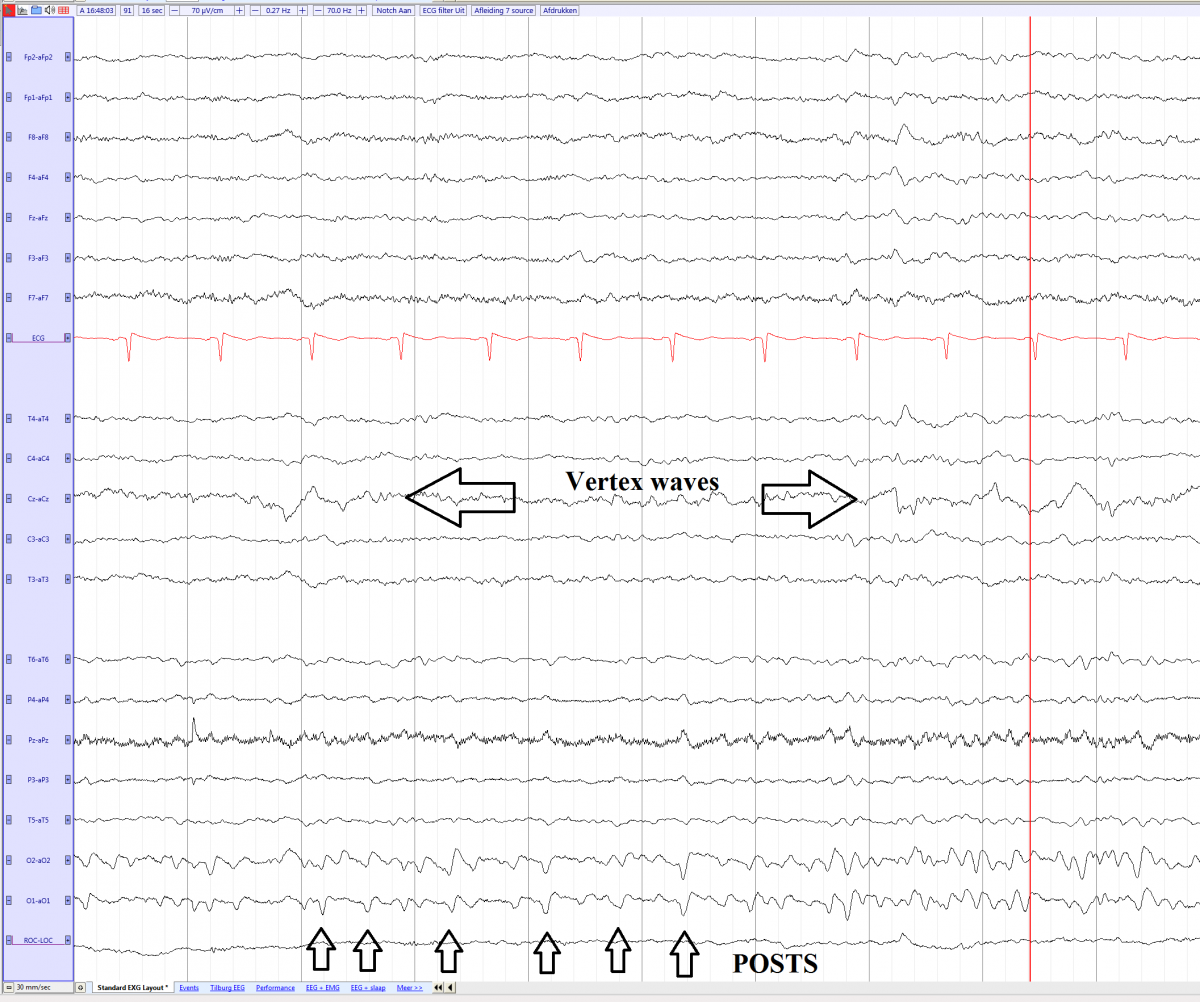

POSTS (Positive occipital sharp transients of sleep) EEGpedia